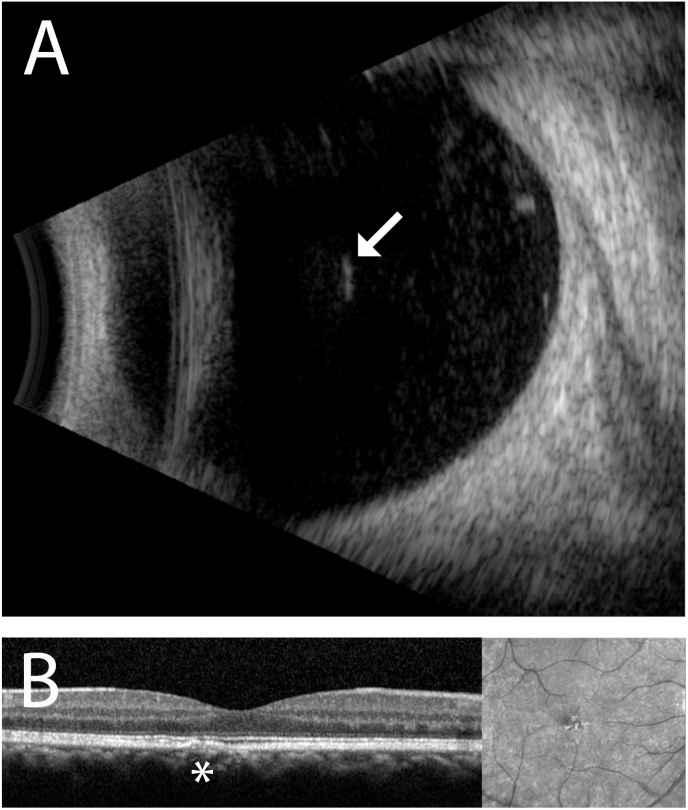

Fig. 3.

A. B-scan ultrasound (Aviso, Quantel Medical) of the right eye localizes the hyperreflective, linear intraocular seta within the anterior vitreous cavity (arrow). Adherent inflammatory deposits are visualized around it. No other intraocular setae are identified within the vitreous cavity. B. Spectral-domain optical coherence tomography (Heidelberg Spectralis, Heidelberg Engineering, Germany) shows a focal, perifoveal region of ellipsoid zone disruption of unclear significance. The finding remained unchanged over the 4 week follow up interval and visual acuity remained stable at 20/20-20/25 in the right eye.